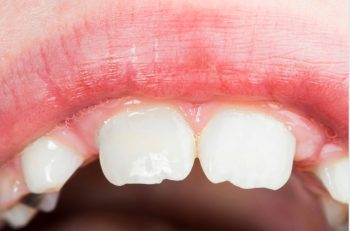

Unlocking the Mystery of Hypodontia: Exploring the Missing Teeth Phenomenon

It seems like common sense; baby teeth fall out, adult teeth come in. But sometimes there are certain teeth that don't ever come in, and it's not because they're impacted or stuck in the gums. When this happens, it could be because a tooth is congenitally missing, which means a person is actually born without a permanent tooth. Another word... read more »